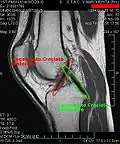

Применяются физикальные методы исследования: осмотр, пальпация, а также сбор анамнеза. Из инструментальных методов для визуализации изменений анатомических структур сустава большое распространение получило МР-исследование. Для оценки целостности и структуры костей, формирующих сустав, предпочтение отдаётся рентгенографии и компьютерной томографии. В настоящее время для диагностики применяют также артроскопию.

МРТ коленного сустава. -

Крестообразные связки. -